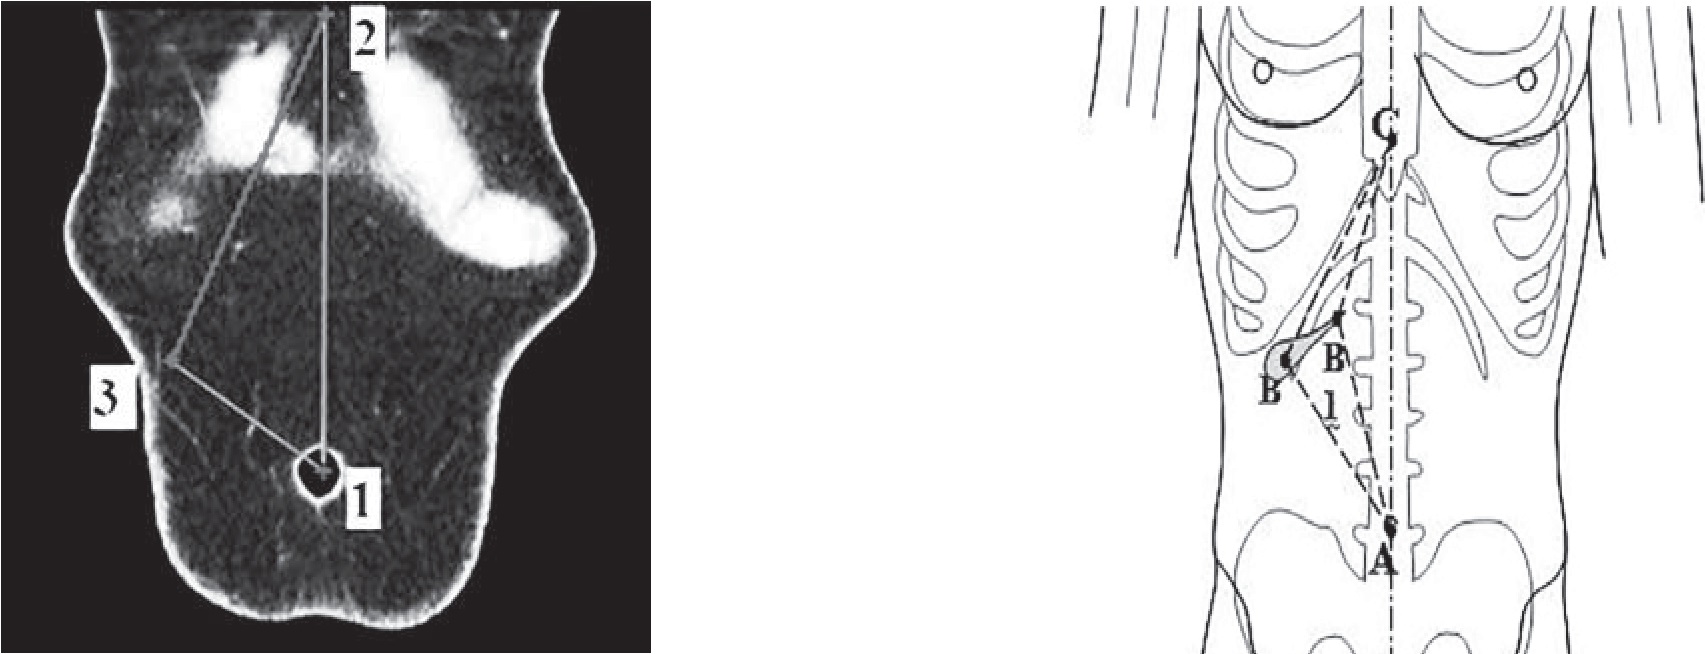

Для уточнения особенностей голотопии желчного пузыря (дна и шейки) нами разработана система координат на плоскости и в пространстве. За точку отсчёта («0») была принята верхушка мечевидного отростка грудины, ось ординат – линия, соединяющая верхушку мечевидного отростка и центр пупка, ось абсцисс – условная линия, параллельная горизонтальной плоскости тела, проходящая через точку «0» и перпендикулярная оси абсцисс (рис. 1), единицы измерения – миллиметры, цена деления шкалы – 1 мм.

Рис. 1. Система координат для определения голотопии желчного пузыря: 1 – точка «0»; 2 – пупок; 3 – проекция дна желчного пузыря (точка Кера); 4 – ось ординат; 5 – ось абсцисс

Между указанными точками проводили линии и формировали отрезки (рис. 4). Отрезок «АС» – расстояние между пупком и вершиной мечевидного отростка, отрезок «АВ» – дистанция между пупком и проекцией дна желчного пузыря на ПБС, отрезок «ВС» – расстояние между вершиной мечевидного отростка и проекцией дна желчного пузыря на ПБС, отрезок «АВ1» – от пупка до проекции шейки желчного пузыря на ПБС, отрезок «СВ1» – от верхушки мечевидного отростка до проекции шейки желчного пузыря на ПБС.

Рис 4. Определение голотопии дна и шейки желчного пузыря: а – изображение ПБС, б – схематическое изображение. Точка 1 (точка А) – пупок; точка 2 (точка С) – вершина мечевидного отростка; точка 3 (точка В) – проекция дна желчного пузыря на переднюю брюшную стенку; точка В – проекция шейки желчного пузыря на переднюю брюшную стенку